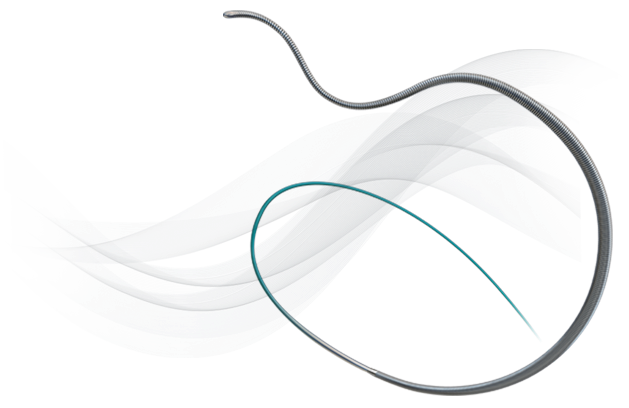

Designed with Micro EMT technology to have an ultra low crossing profile and exceptional steerability, JUDO Guidewires are ideal intraluminal crossing wires for complex lesions.

Superb ability to probe and cross complex lesions and fibrous tissue.

Outstanding flexibility to maintain position on the true lumen while maneuvering through complex lesions and tortuosity.

Exceptional torque response for precision steering in tight lesions.